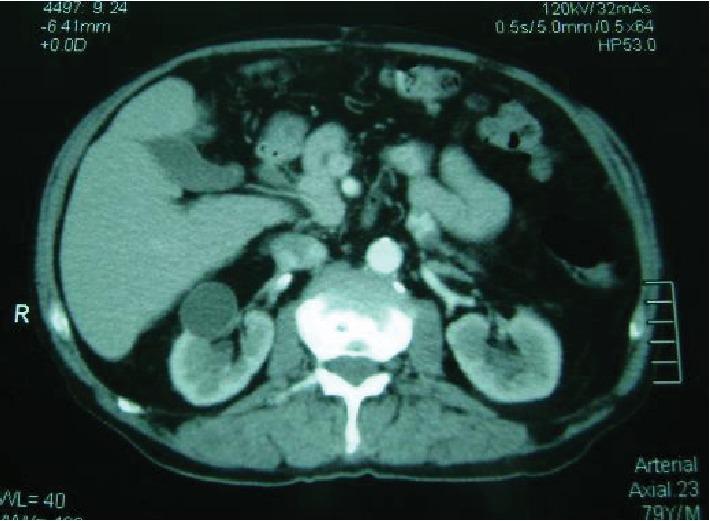

The occurrence of metastatic tumors in the orofacial region is rare and may represent the first clinical manifestation of occult malignant disease. An orofacial lesion diagnosed as a metastatic tumor from a renal cell carcinoma in a 68-year-old man is reported. This metastatic tumor caused significant facial asymmetry involving the parotid gland and mandible regions, and the patient died four months after diagnosis. Here, we discuss the clinical aspects, the diagnostic approach, and the importance of early diagnosis to obtain a better response to treatment and provide longer survival time.

口腔颌面部转移性肿瘤的发生较为罕见,可能是隐匿性恶性疾病的首发临床表现。本文报道了一例68岁男性患者,其口腔颌面部病损经诊断为肾细胞癌转移瘤。该转移性肿瘤导致腮腺和下颌骨区域出现明显的面部不对称,患者在诊断后四个月死亡。在此,我们讨论了该病例的临床情况、诊断方法以及早期诊断对于获得更好治疗反应和延长生存时间的重要性。